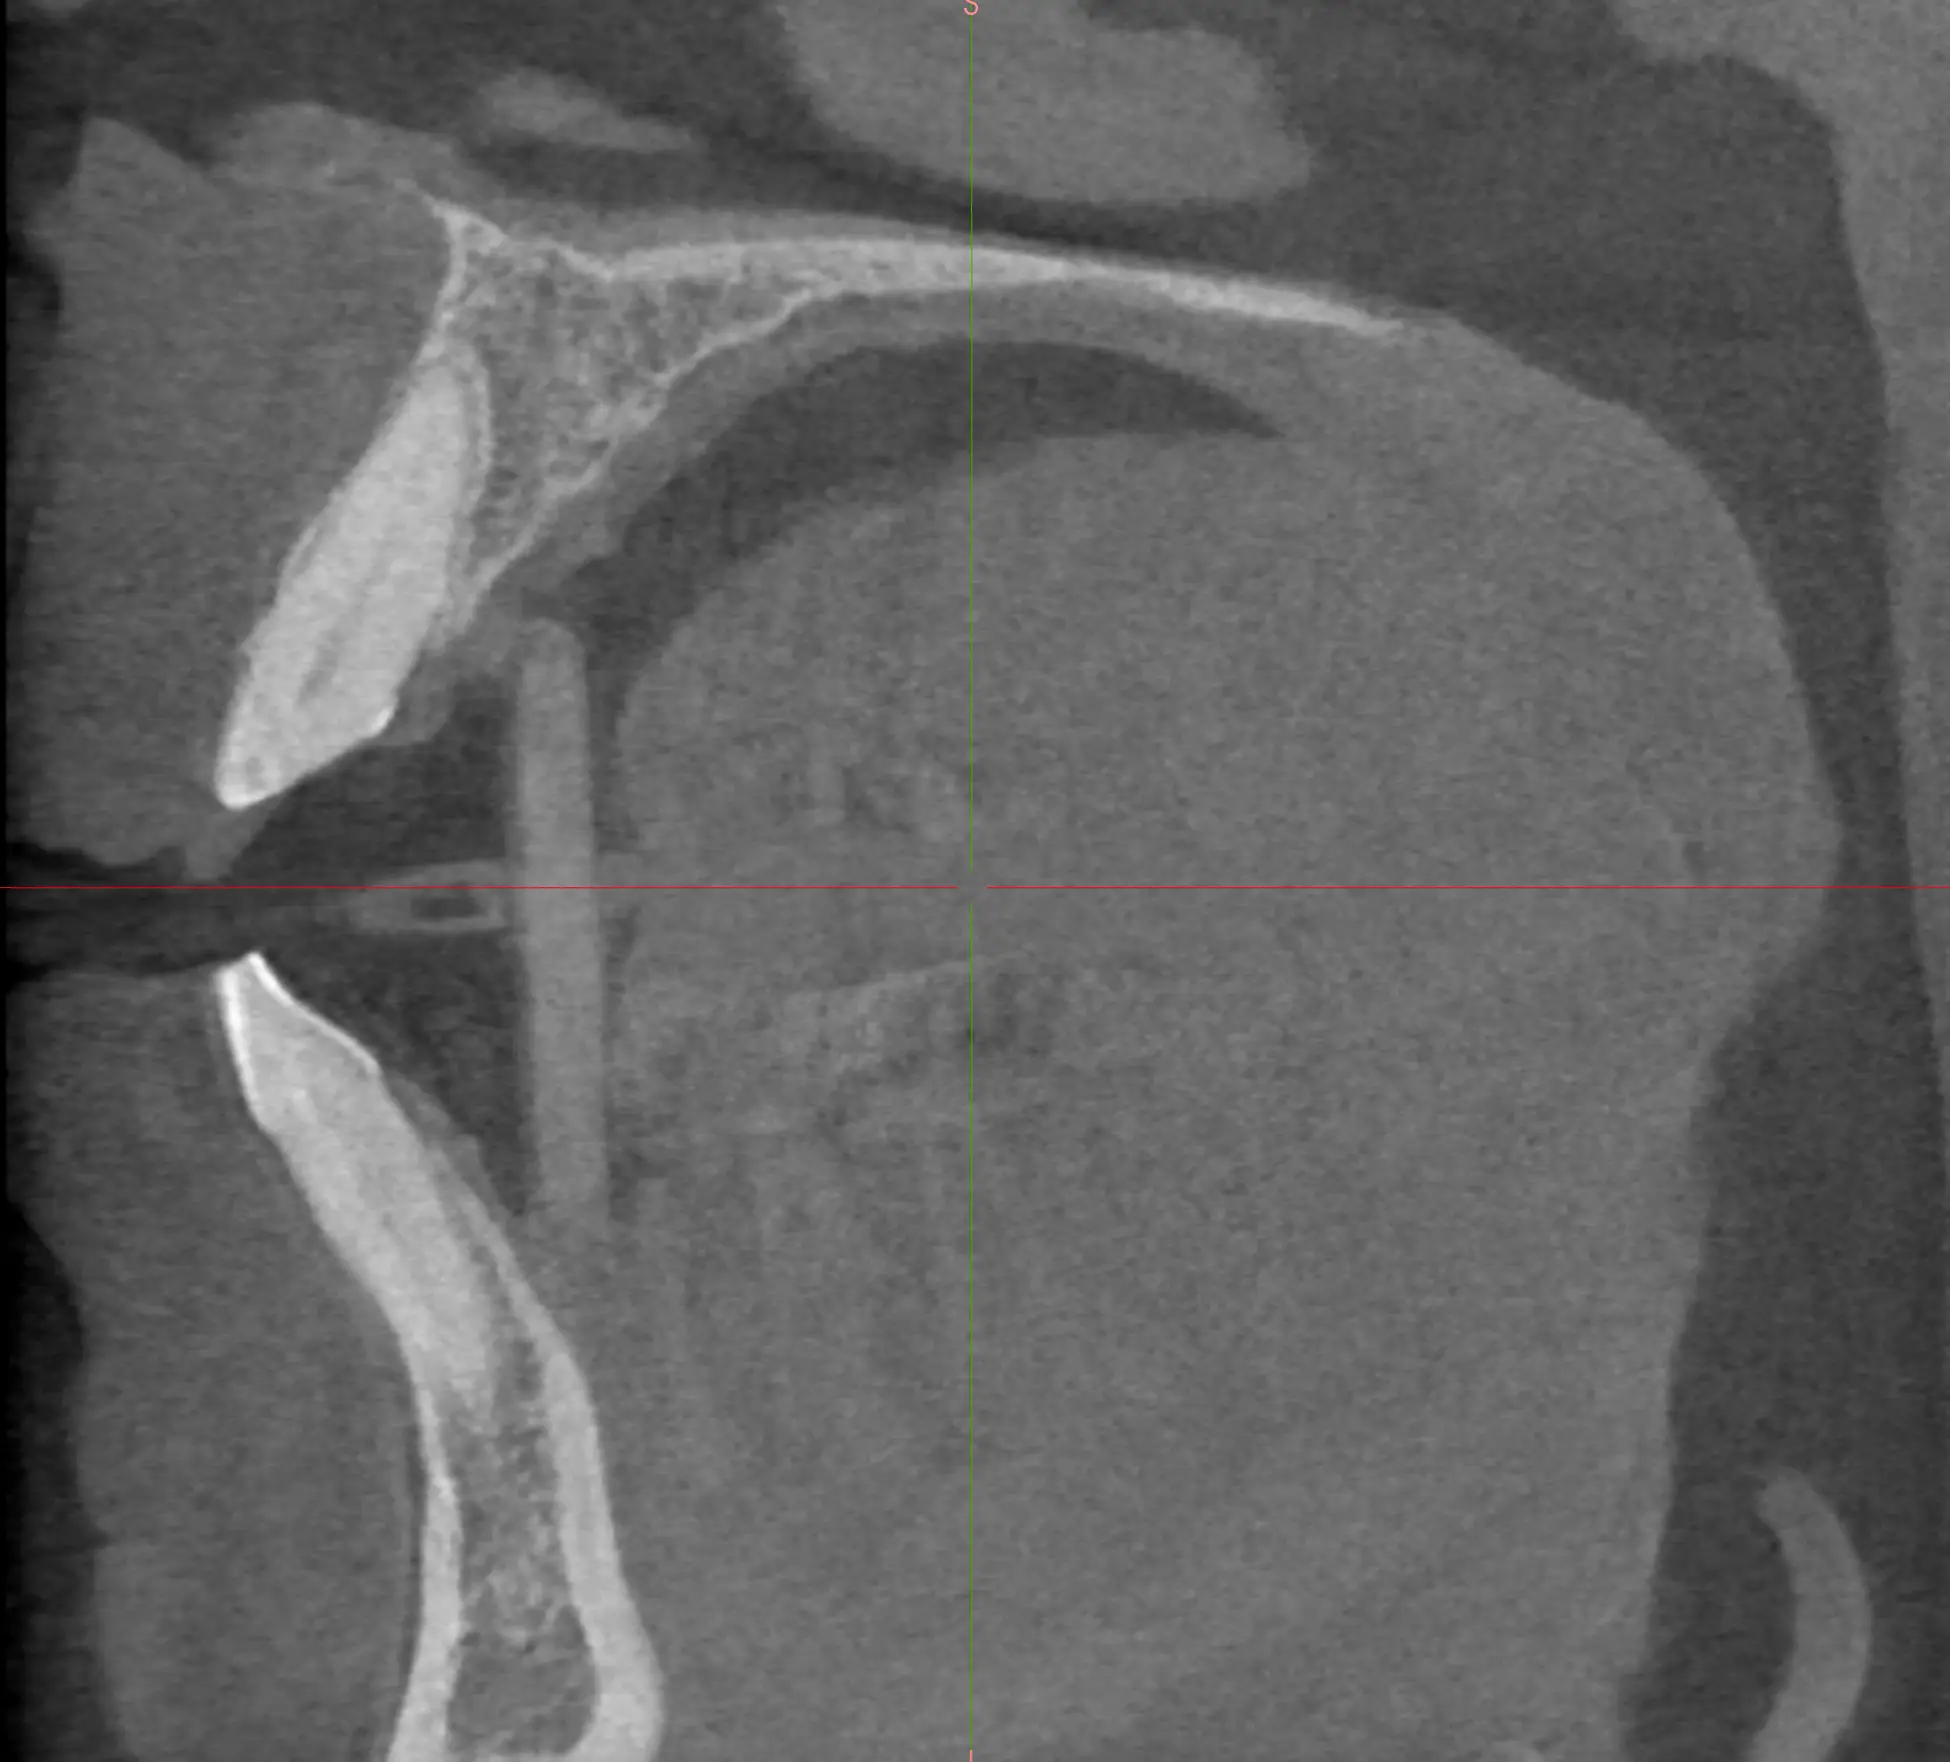

Patient 2